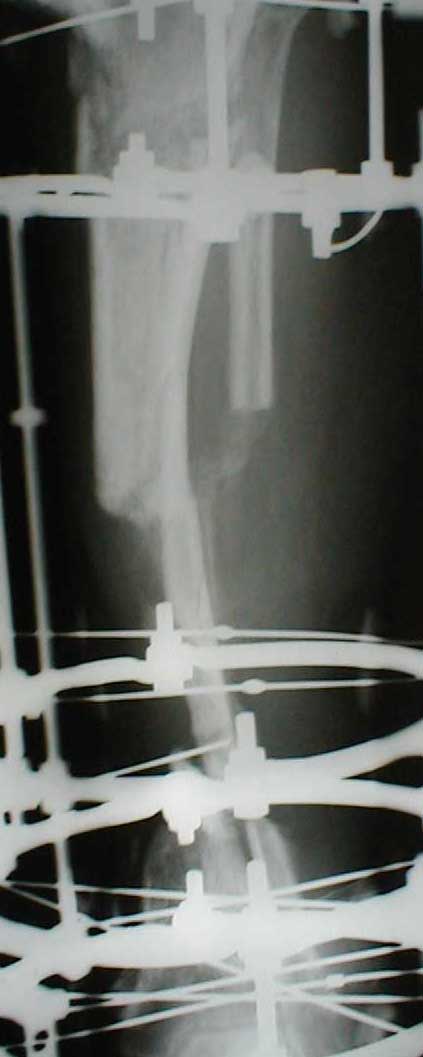

Zdes' snimky posle poslednego montazha apparata prilagaiutsa

Yours Castro

Кликните для загрузки файла IMG_0501.jpg

Может быть не совсем в тему, но... Скажите, а чем вызвана такая необычная компоновка аппарата: кольцевидный фиксатор и стержни? На первый взгляд так теряются преимущества монолатеральной стержневой фиксации (легкость перевязок) без достаточной компенсации достоинствами классического ВКДО Илизарова?

Андрей Крылов 02 Июнь 2005, 20:10

"Необычная" фиксация, предполагает осуществление максимальной стабильности проксимального фрагмента б\б кости. Как ее добиться - дело лечащего врача. При всем уважении к монолатеральным фиксаторам, лучше пожертвовать неудобствами при перевязках, чем нестабильностью фрагментов. Если поставлена цель сохранения конечности, то на данном этапе стабильность это - пункт № 1.